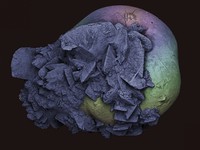

Kidney stone, SEM.

MacKenzie, Kevin.Date: 2013